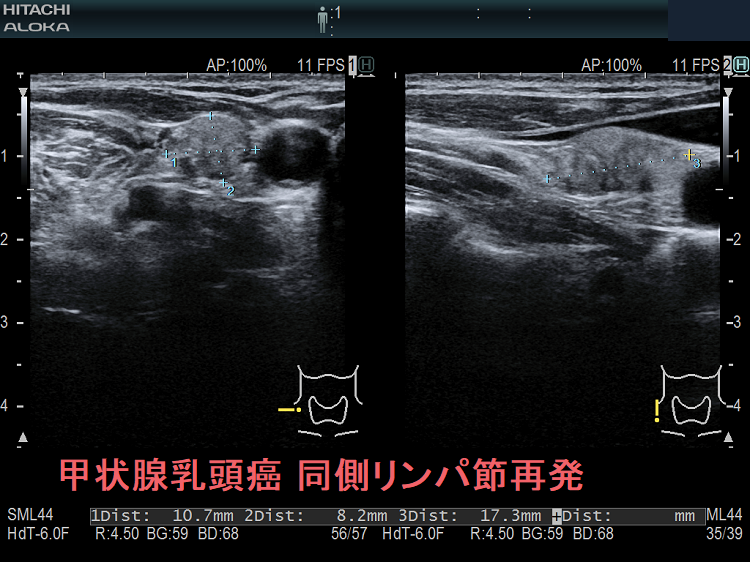

甲状腺乳頭癌の同側(切除した側)と対側(切除していない側)のリンパ節再発を同時に認めた症例

次の写真は甲状腺半葉切除(右葉)切除後リンパ節再発です。左右とも総頚動脈外側のリンパ節再発です。

甲状腺乳頭癌の同側(切除した側)のリンパ節再発 超音波(エコー)画像

甲状腺乳頭癌の同側(切除した側)リンパ節再発 超音波(エコー)画像;等エコー、いびつな形で、周囲との境界が一部不明瞭化して浸潤を疑われる。リンパ門は消失し、砂粒状石灰化が著明。

甲状腺乳頭癌の同側(切除した側)のリンパ節再発 超音波(エコー)画像 ドプラーモード

甲状腺乳頭癌の同側(切除した側)リンパ節再発 超音波(エコー)画像 ドプラーモード;内部に異常な走行の血管を認め、血流豊富。

甲状腺乳頭癌 対側(切除していない側)リンパ節再発 超音波(エコー)画像

甲状腺乳頭癌 対側(切除していない側)リンパ節再発 超音波(エコー)画像;等エコー、いびつな形で、周囲との境界が一部不明瞭化して浸潤を疑われる。リンパ門は消失。

甲状腺乳頭癌 対側(切除していない側)リンパ節再発 超音波(エコー)画像 ドプラーモード

甲状腺乳頭癌 対側(切除していない側)リンパ節再発 超音波(エコー)画像  ドプラーモード;内部に異常な走行の血管を認め、血流豊富。